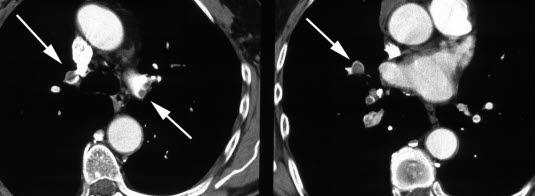

Diagnosen kan være vanskelig å stille. Mistanke om lungeemboli på grunnlag av sykehistorien fører alltid til akutt innleggelse på sykehus. Der vil det bli tatt blodprøver, blant annet for å påvise eller utelukke andre sykdommer som kunne medført disse plagene. Lungene vil bli grundig undersøkt, og en spesiell CT-undersøkelse av blodårene i lungene kan gi sikkert svar.